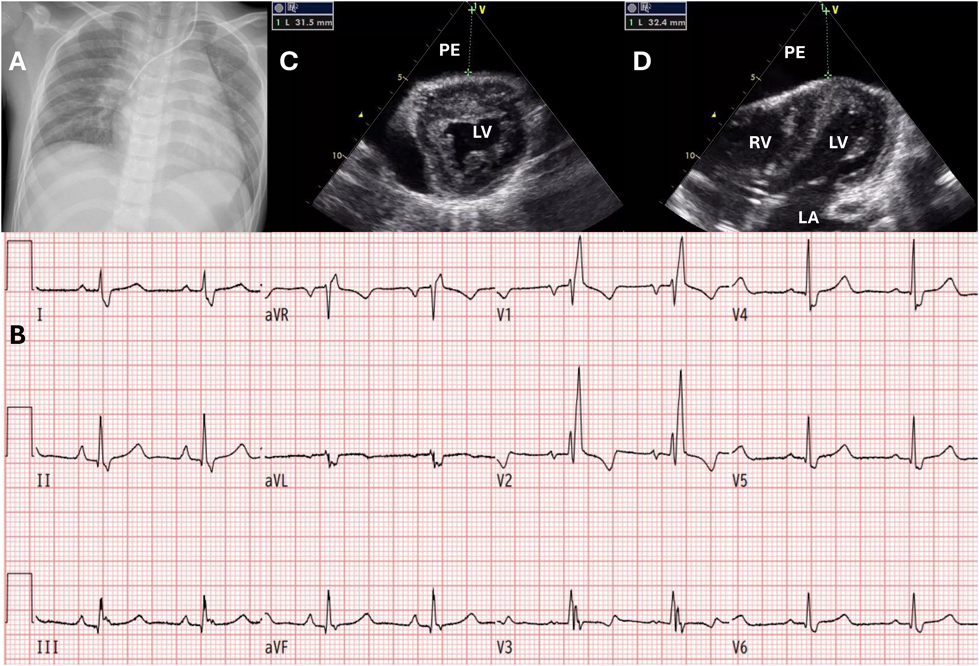

入院時の血液検査で代謝性アシドーシスを認めた.D-dimerは10.2 µg/mLと高値,CK-MBは3.0 ng/dLと軽度高値,トロポニンIは299 pg/mLで高値,BNPは374 pg/mLに上昇していた.ASO,リウマチ因子,甲状腺刺激ホルモンに異常を認めなかった.感染症検査として,多項目ポリメラーゼ連鎖反応(polymerase chain reaction: PCR)パネル検査を行ったがいずれも陰性だった.βDグルカンや結核菌特異的インターフェロンγ検査は陰性,その他提出していた血液学的検査で,CoxA2-IgG抗体と,CoxA9-IgG抗体が32倍(NT法)と後日判明した.胸部X線写真では心胸郭比(cardiothoracic ratio: CTR)59%と心拡大および肺うっ血像を認めた(Fig. 1A).心電図検査では,VSD術後から認めていた完全右脚ブロック波形を認め,全体的にやや低電位だったが,過去の心電図と比較してST部分の変化は認めなかった(Fig. 1B).心臓超音波検査では心臓前面に4 cm程度の心嚢水貯留を認め,右室は圧排されていた(Fig. 1C, D).

Fig. 1 入院時画像所見

A:胸部X線写真半坐位撮像.59%と心拡大を認め,肺うっ血像を認めた.B:心電図.術後より完全右脚ブロックを認めていた.過去と比較して明らかなST変化を認めなかった.C:心臓超音波検査左室短軸像.右室の前面に3 cm程度の心嚢水貯留を認めた.D:心臓超音波検査四腔断面像.心尖部に3 cm程度の心嚢水貯留を認めた.LA:左心房,LV:左心室,PE:心嚢水,RV:右心室.